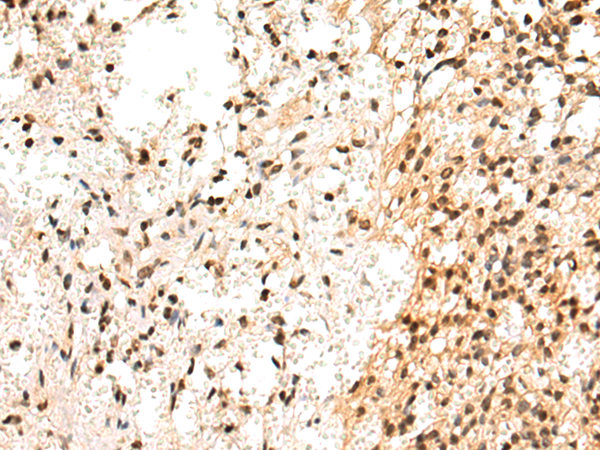

IHC positive control: |

Human breast cancer and Human prostate cancer |

IHC Recommend dilution: |

50-200 |